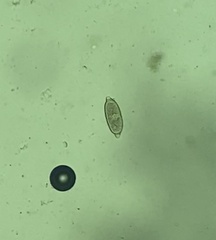

Images from inaturalist.org observations: